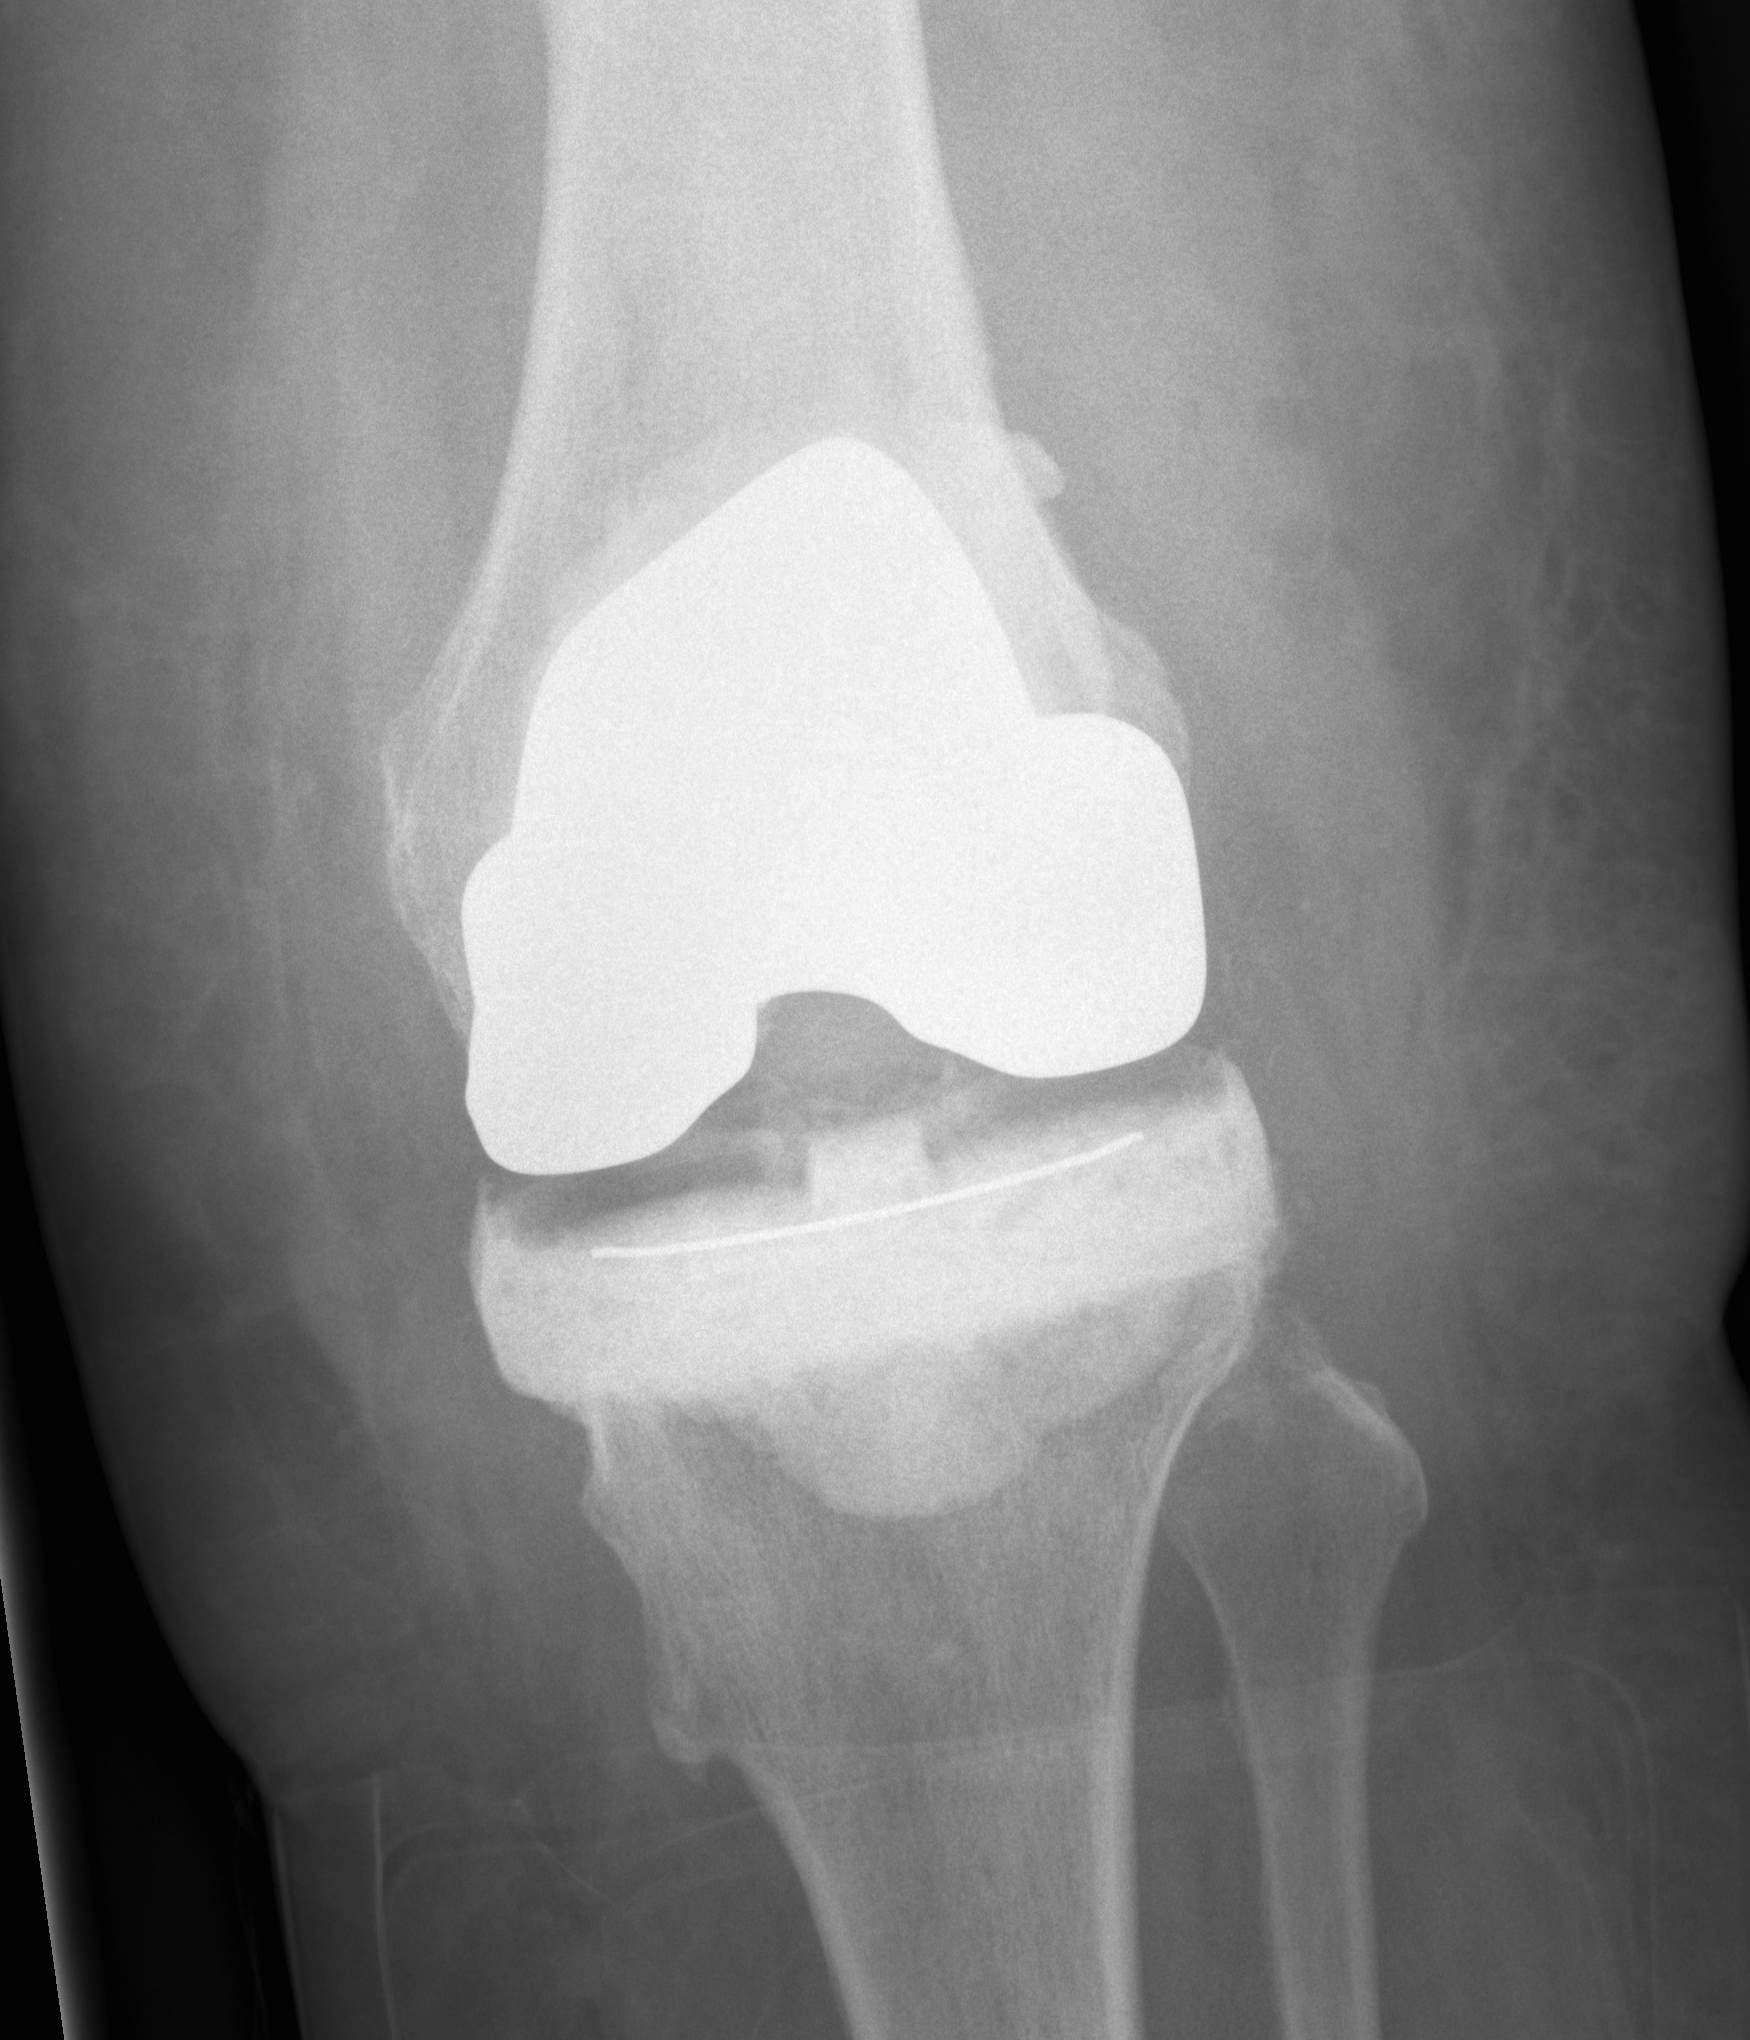

2nd Stage

Careful removal of prosthesis

Insertion of stemmed revision prosthesis with augments

- constraint as required

- antibiotic cement